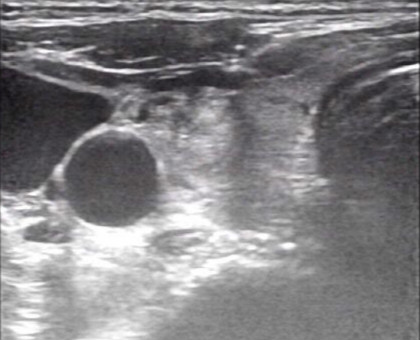

超声引导下的甲状腺结节细针穿刺活检术(US-FNAB)是指在高频超声引导下,应用无菌穿刺针(通常22-25G的甲穿专用针)穿刺甲状腺结节可疑部位,抽取部分结节成分送细胞学病理检测的一种鉴别甲状腺良恶性的方法。甲状腺结节是临床上最常见的甲状腺病变。超声在甲状腺结节评估中具有很高的敏感性及特异性,然其仅能对甲状腺结节的实现初步评估,无法给予明确的定性诊断。目前超声引导下细针穿刺活检已成为甲状腺结节评估的金标准。一方面提供甲状腺结节的重要信息如回声情况、边界、形状,有无钙化、血流情况等。另外一方面赋予细针穿刺活检精确定位的优势,极大降低了假阴性穿刺及取样的不满意情况。